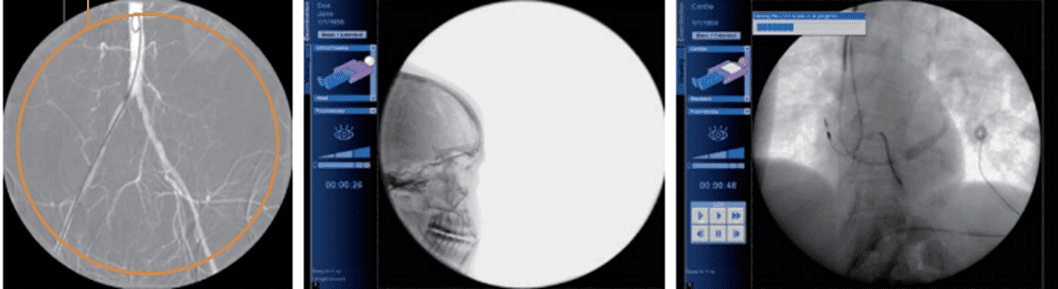

Рентген С-дуга – це апарат, який отримав свою назву від специфічної конструкції, що повністю повторює букву «С». Таке високотехнологічне обладнання активно використовується як у класичних рентген-кабінетах, так і в операційних через високу точність візуалізації інформації. Відрізняється універсальністю, швидкою роботою, чітким зображенням і повною безпекою пристрою.

Конструкція рентген апарату досить специфічна. Штатив має дугоподібну форму. На ньому розташована рентгенівська трубка і система охолодження, яка потрібна для проведення довгих операцій. У деяких моделях для поліпшення якості зображення також є цифровий рентгенівський детектор, більшість із них оснащено підсилювачами рентгенівського зображення.

Головна особливість такої конструкції – компактність. Такий апарат поміщається навіть у невеликі кабінети, а портативну модель (яка не фіксується на стелі або підлозі) можна активно переміщати клінікою.

С-дуга активно використовується для діагностики в травматології, хірургії та стоматології. Серед переваг такого обладнання також: